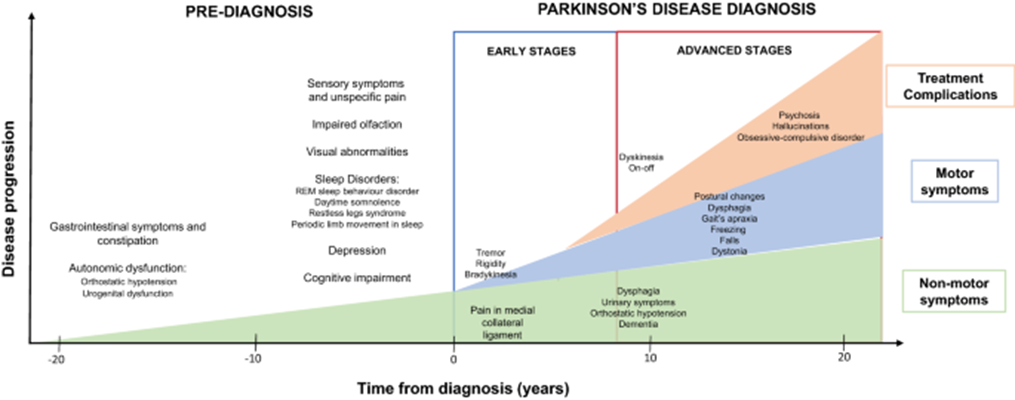

Parkinson's disease progression

Chronology of clinical symptoms in Parkinson’s disease. Schematic representation of the diagnosis (even 10 to 20 years before the onset of the disease) and motor/non-motor symptoms in early and advanced Parkinson’s disease, with clinical and other iatrogenic symptoms.

- Non-motor symptoms of PD: They can occur earlier in the disease before motor symptoms emerge and may be present throughout the course of disease. These are: